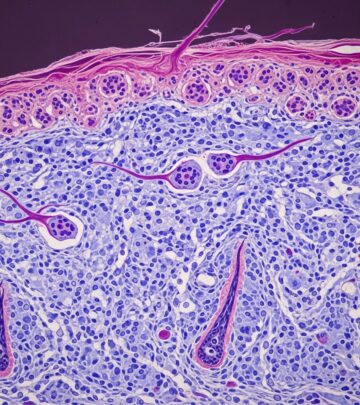

Radiation Dermatitis Pathology: 4 Essential Histologic Findings